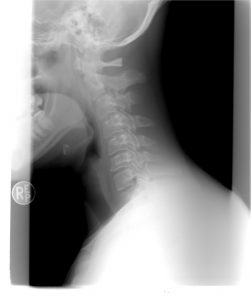

Proste ćwiczenia redukujące napięcie i ból w odcinku szyjnym kręgosłupa

Obecnie wiele osób cierpi na bóle szyi bądź karku. Oto doskonałe ćwiczenie, które mają za zadanie zmniejszyć napięcie i przynieść ulgę w doskwierającym bólu. Ćwiczenie cechuje się także szybkim odczuciem ulgi i redukcji napięcia.